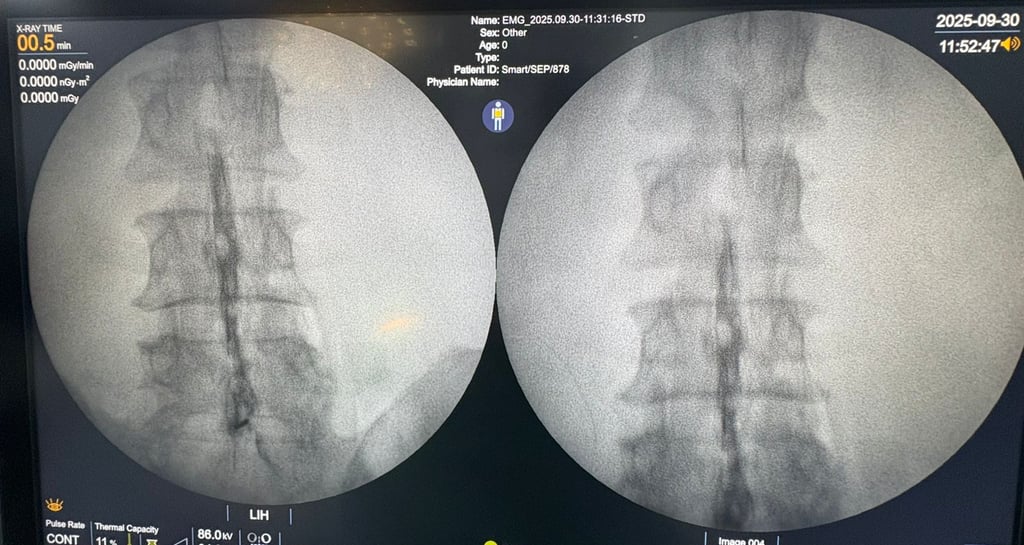

Our treatments use image-guided injections and nerve blocks to target pain precisely.

Snapshots of healing moments at Dolocure.